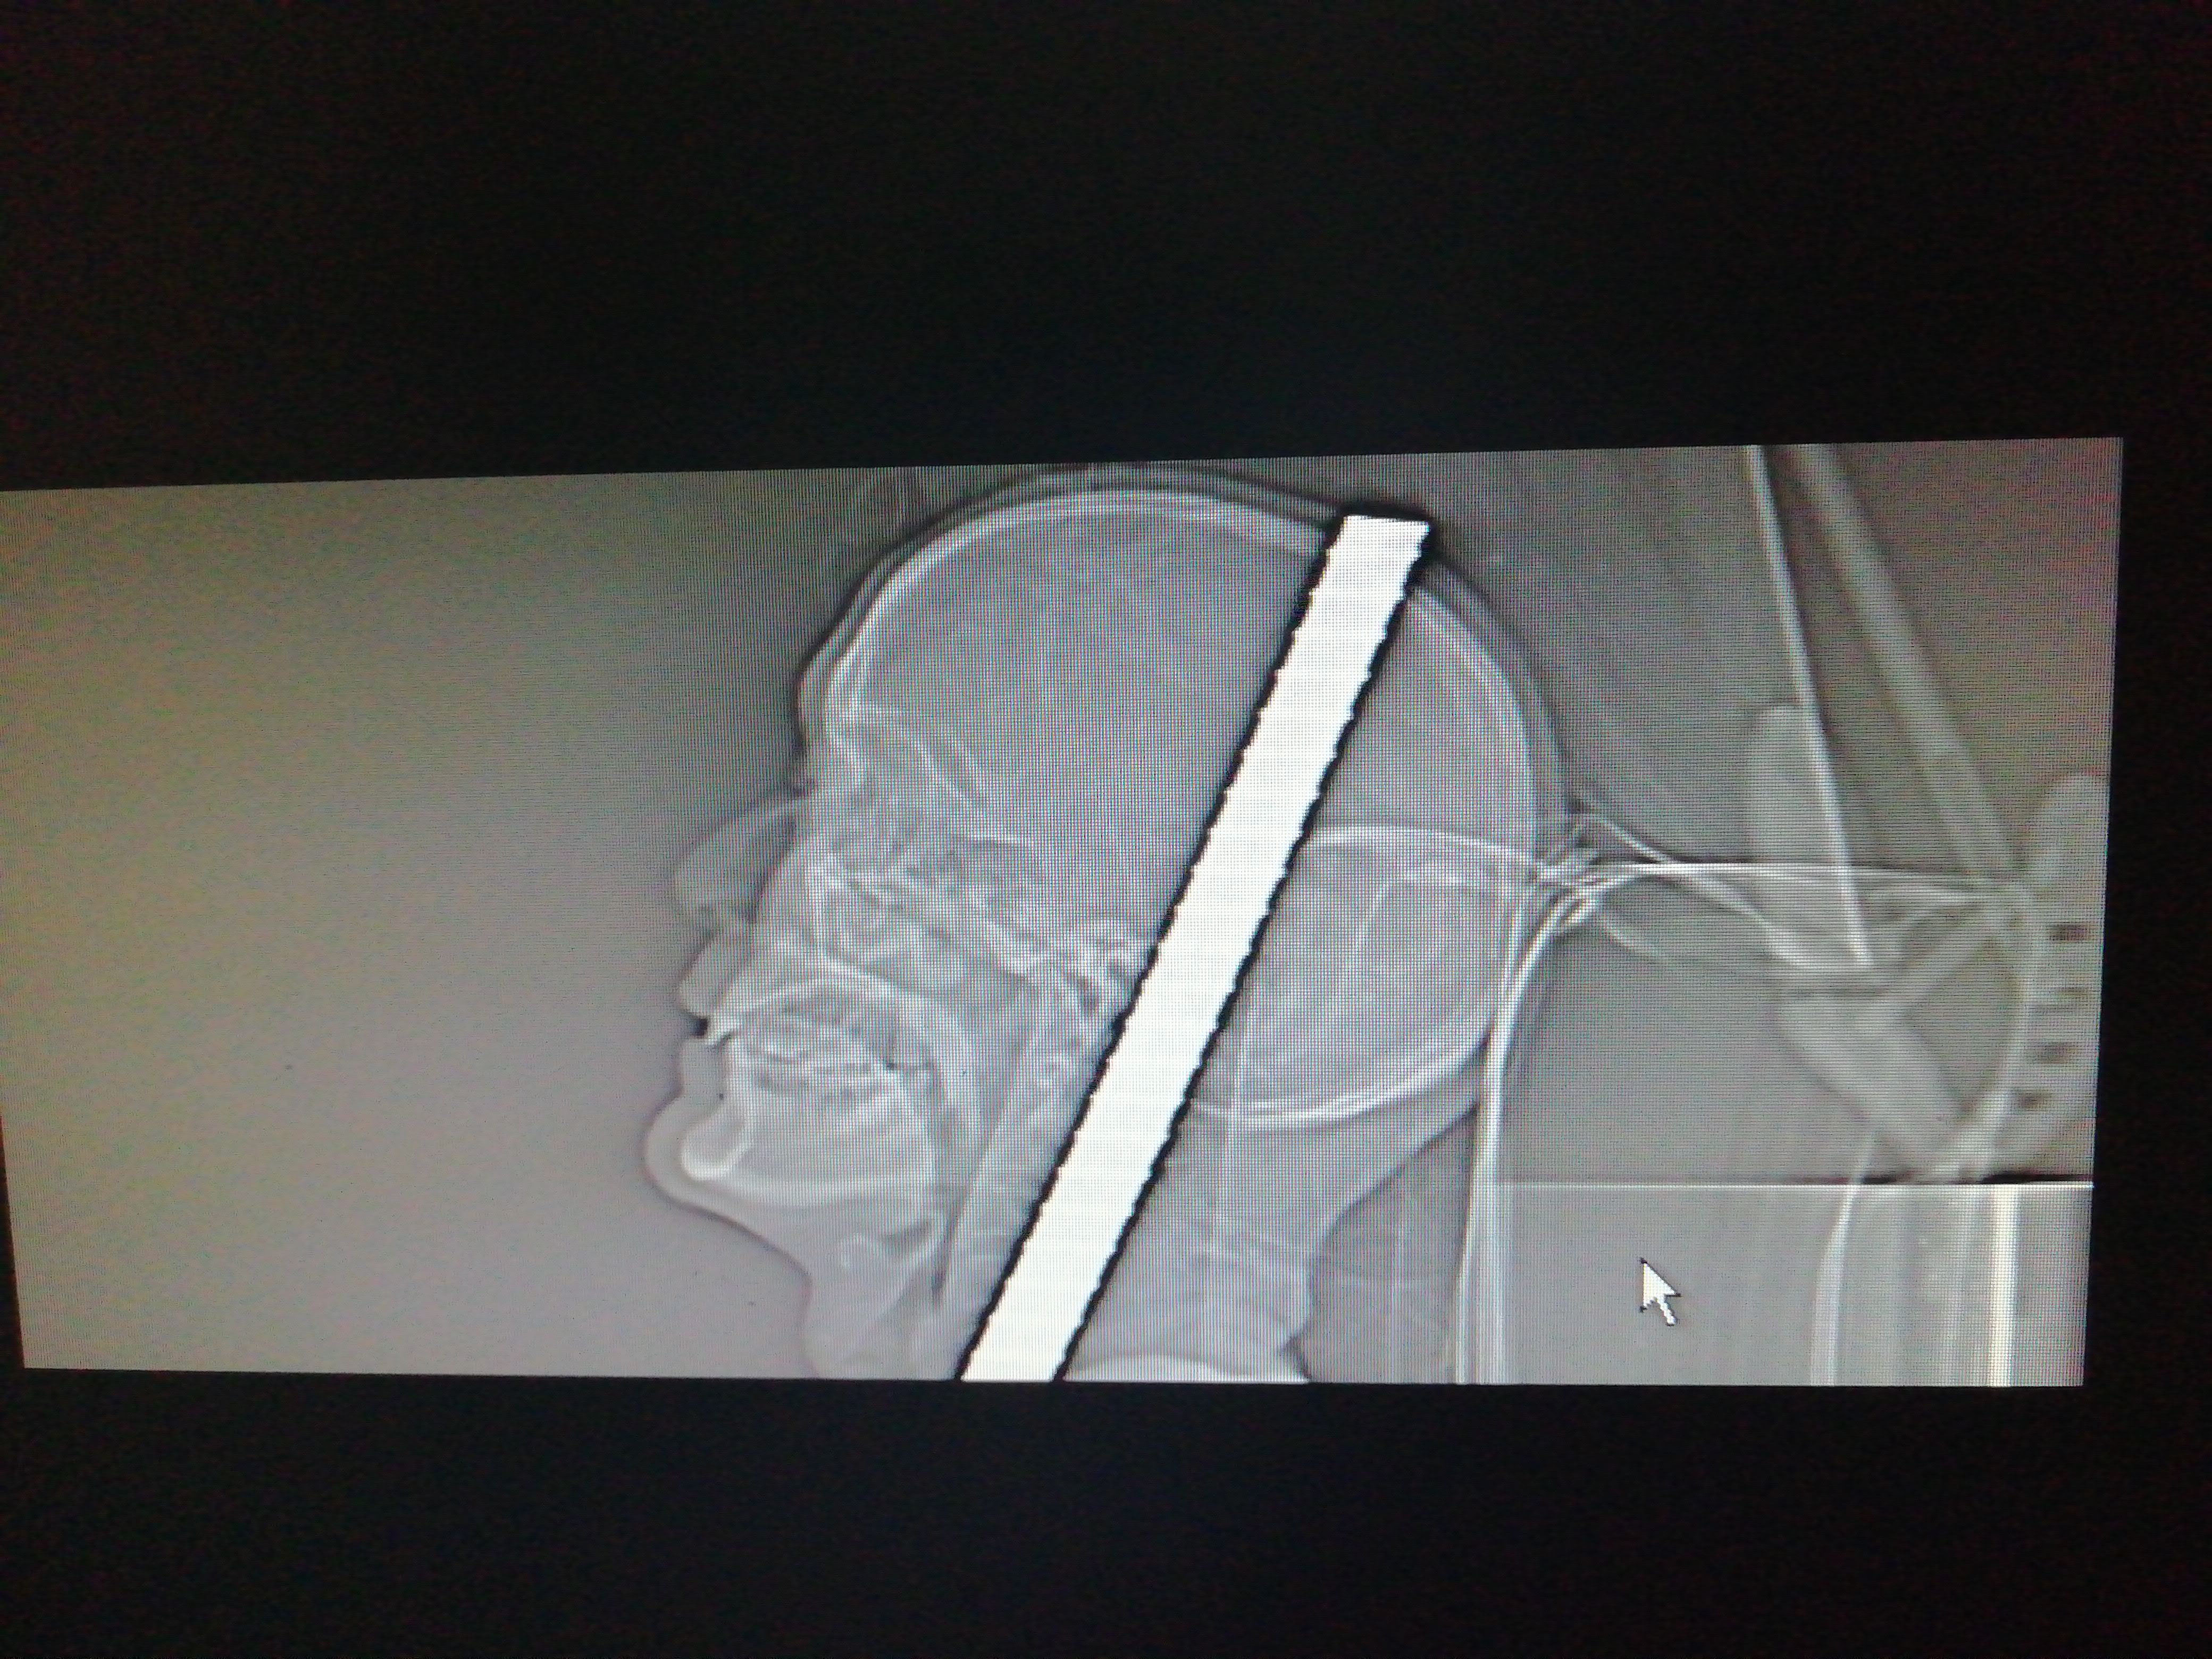

晚上9时许,余某抵达新桥医院急诊科,医院立即为余某开通了创伤急救“绿色通道”,并迅速实施抢救,通过检查发现:其体内有两根钢筋,直径约2厘米,一根是从左侧颞部穿透头皮,大约有15公分长;另一根从右侧上臂直接插进,骨头已经被直接折断了;另胸部有30厘米长的软组织挫裂伤,全身多处有软组织伤,存在生命危险,需要及时手术将钢筋取出!

“右上臂是盲管伤,左侧颞顶部管通伤。”在新桥医院急诊科会议室,在该院医务处的组织下,急诊科周人杰主任、创伤中心宗兆文主任、神经外科裴玉春住院总等10余位专家在现场查看受伤余某身上每根钢筋的位置、走向,可能伤及的血管和神经等,根据丰富的临床经验,预判了手术可能发生的危险,做出了细致周全的急救方案和应对策略。